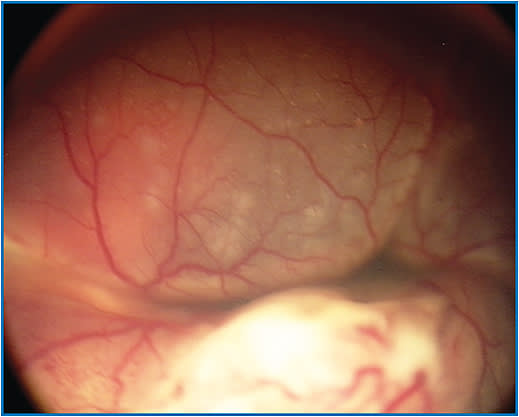

Generally speaking, group D eyes are those with nondiscrete growth or nonlocalized seeding (Figure 1). However, while the CHLA version defines D eyes as having a tumor with “exophytic or endophytic qualities, diffuse/extensive vitreous or subretinal seeding, and/or retinal detachment in >1 quadrant,”2 the Philadelphia system describes the same tumors as having “subretinal and/or vitreous seeds >3 mm from the tumor margin, occupying ≤50% of the globe,”3 and the COG criteria includes the presence of vitreous and/or subretinal seeding (in addition to subretinal fluid) and increases the radius from the tumor margin to >6 mm.4 The discrepancies in these criteria, among others, have undermined the value of the IIRC in assessing, comparing, and communicating treatment outcomes. Moreover, a review of the literature by Dr. Abramson and colleagues revealed that only 3 out of 20 papers communicating outcomes of eyes classified according to the IIRC specified which IIRC version was used.1